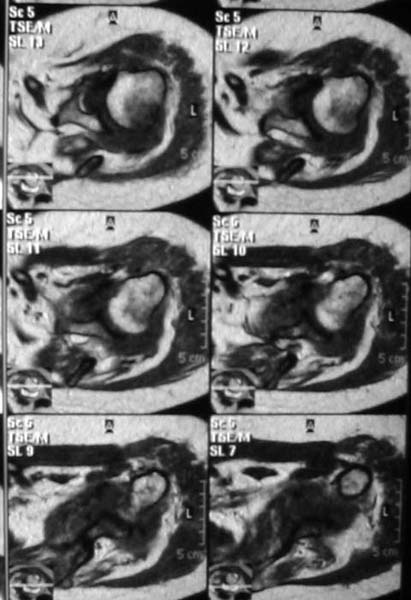

Уважаемые коллеги! Женщина, 60 лет. 3 недели назад упала с упором на отведенную левую руку. Почувствовала боль в левом плечевом суставе. За помощью не обращалась. 2 недели "мази и припарки". Затем - рентгенограмма (r1 и r2), жалобы на боли, ограничение движений...

Активное отведение 80 гр., при пальпации - головка плечевой кости безболезненно вправляется и тут же самостоятельно вывихивается. Наложена косыночная иммобилизация, рентгенография (r3) и МРТ. В нашем диагностическом центре МРТ исследование плечевого сустава выполнено впервые, опыта у нас маловато :(. Вопросы: уточнение диагноза? какие исследования провести? тактика лечения?

МРТ1 МРТ2 МРТ3 МРТ4